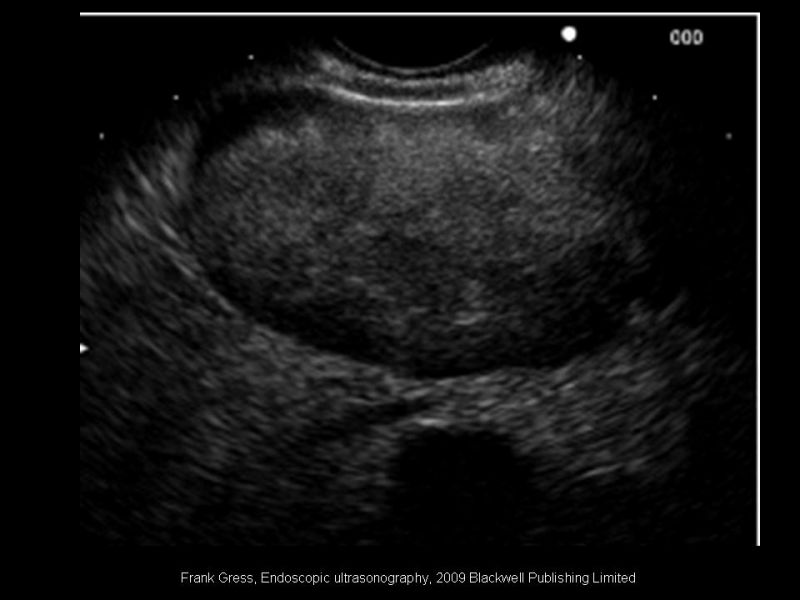

Rol actual de la endosonografía en patología biliopancreática

Especialidad: Hepatobiliopancreático | Autor: Dr. Rodrigo Subiabre Ferrer